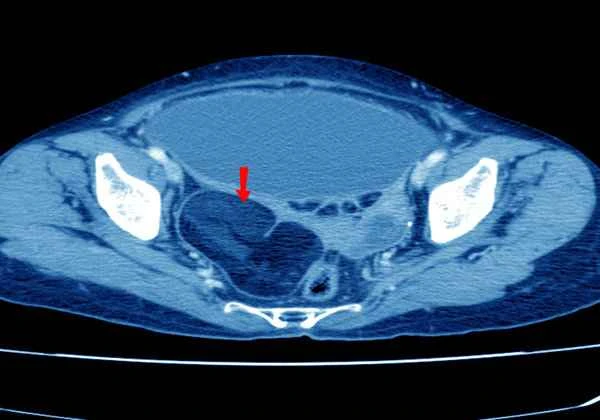

Determining the location of intestinal obstruction is typically done through clinical symptoms, physical examination, and imaging studies. Doctors will assess the patient's symptoms, such as abdominal pain, vomiting, and bloating, combined with physical examination findings like abdominal tenderness and changes in bowel sounds. Imaging techniques such as X-rays, CT scans, or ultrasound will be used to observe the distribution and morphological changes of intestinal gas to pinpoint the exact location of the obstruction. Each of these methods has its advantages and disadvantages, and doctors will choose the most appropriate method based on the specific circumstances.